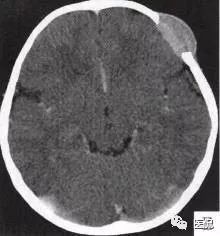

颅脑CT示:图A〜D,CT平扫示左侧额骨、蝶骨见溶骨性骨质缺损,边界清晰,周围无硬化边,伴有软组织肿块向脑外生长,边缘光滑,脑内无明显侵犯;

图E、F,横、 矢状位CT增强示软组织肿块轻度均匀强化,两病灶间亦见强化软组织影;

2.定位诊断:额骨、蝶骨均可见局限性骨质破坏,穿破颅骨内外板,见软组织肿块突向脑外;肿块与硬脑膜界限清楚,脑实质无侵犯;应考虑颅骨来源,向颅外侵犯。

②颅骨多处溶骨性破坏,穿透颅骨内外板;

③骨破坏无 硬化边,边缘光整,无膨胀;

④软组织肿块形态规则,边缘光滑;⑤脑膜及脑组织无侵犯, 表现为推压或移位。后三点均支持为良性肿块,结合年龄、实验室检查等,诊断不难。本例经病理(图I)证实为:嗜酸性肉芽肿。